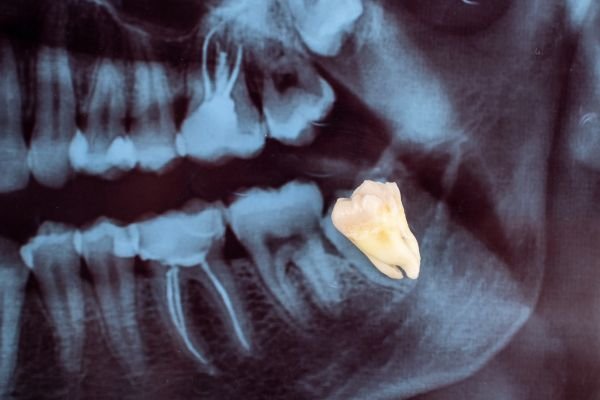

4. Impaction

• A wisdom tooth can become stuck under the gums or against neighboring teeth, forcing it to grow in a tilted or crooked way.

Sometimes, the wisdom tooth’s natural eruption path isn’t straight, causing it to grow at an angle. This lack of room or space can result in a number of harmful effects on your overall dental health. When this occurs they are said to be impacted, indicating their inability to erupt into an alignment, which will allow them to be able to function in the chewing process.

There are several types of impactions:

Soft Tissue Impactions: There is adequate jawbone to allow the wisdom tooth to erupt but NOT enough room to allow the gum tissue to recede to allow adequate cleaning of the tooth.

Partial Bony Impactions: There is enough space to allow the Wisdom tooth to partially erupt. It cannot function in the chewing process and creates cleaning problems, among others.

Complete Bony Impactions: There is no space for the tooth to erupt. It remains totally below the jawbone or if even partially visible requires complex removal techniques.

Unusually Difficult Complete Bony Impactions: The impacted Wisdom tooth is in an unusual and difficult to remove position. This situation can also arise when the shape of the jawbone and other facial structures make removal of this tooth significantly more difficul